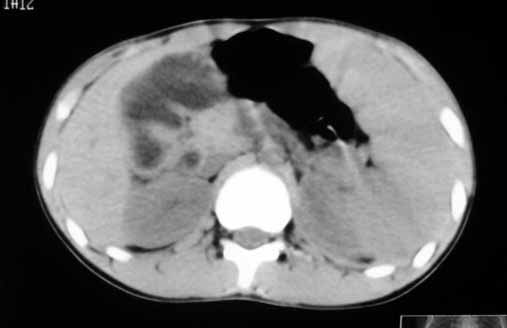

以下是引用zhangzhongshou在2007-5-22 21:04:00的发言:[br]1、脾肿大[br]2、脾脏低密度影,血管瘤?脾梗塞不能除外,建议增强扫描。

以下是引用dyqct在2007-5-22 20:45:00的发言:[br]巨脾,可疑梗塞,建议增强、查血象进一步检查

以下是引用liuyue在2007-5-23 7:57:00的发言:[br]腹主动脉周多个肿大淋巴结,脾大伴三角形低密度影,肠腔积气,考虑:1淋巴瘤2脾大伴梗塞3肠腔积气(肿大淋巴结压迫所致)